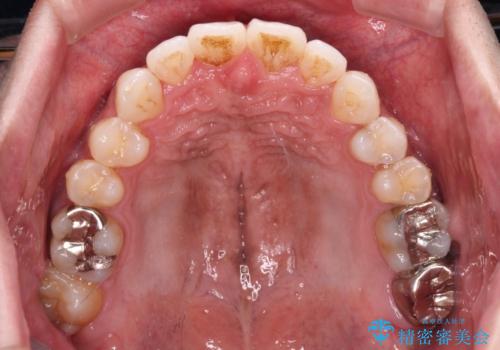

上顎の狭い歯列をインビザラインで拡大

奥歯はクロスバイトとなっているので上顎は側方拡大を行いつつ、上下全体の叢生をインビザラインにより改善することとしました。

治療途中でクリーニングやホワイトニングを行い、歯列が整うと同時に明るい口元となりました。